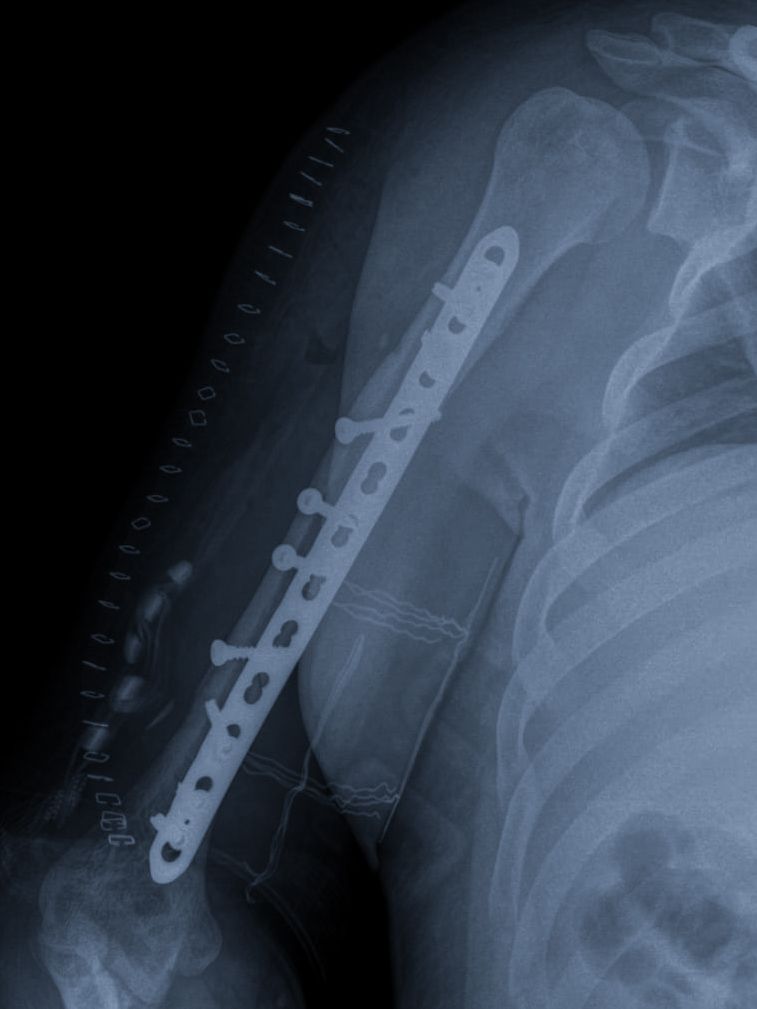

Reparación de fracturas de cúbito y radio

Las fracturas de la muñeca y el antebrazo son lesiones que por su localización ademas de ser sumamente dolorosas, pueden llegar a ser sumamente incapacitantes, pues una lesión en esta zona que no se trate adecuadamente puede limitar severamente la función del brazo y en consecuencia de la mano. Nuestro compromiso es poner todo el conocimiento y experiencia de nuestras manos en la mejor atención de su fractura para una adecuada función y calidad de vida.